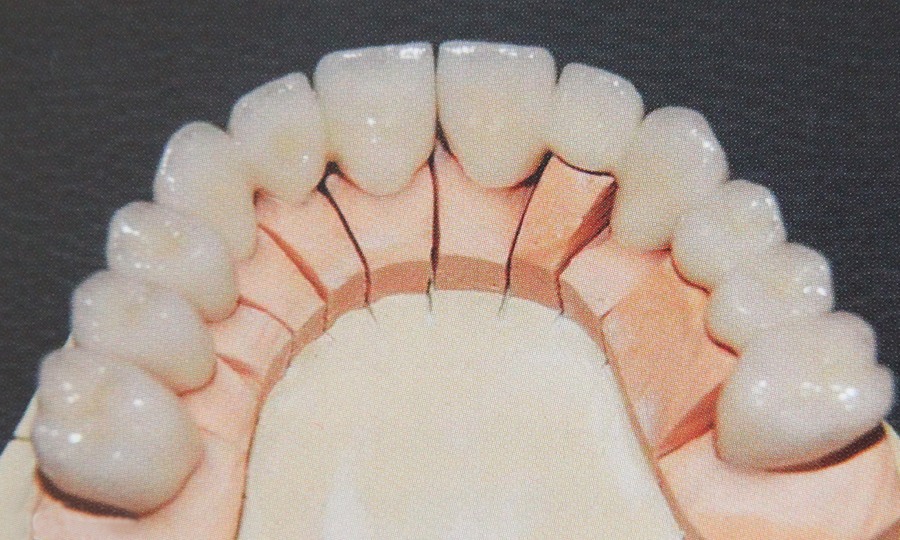

Tehnicile adezive directe de lucru cu materiale bazate pe rasini composite reprezinta o modalitate excelenta de restaurare estetica si minim invaziva a dintilor frontali. Obtinerea rezultatelor estetice asteptate este legata indesolubil de alegerea si utilizarea corecta, conform indicatiilor, a materialelor si tehnicilor de lucru adecvate, fiecarei situatii clinice.